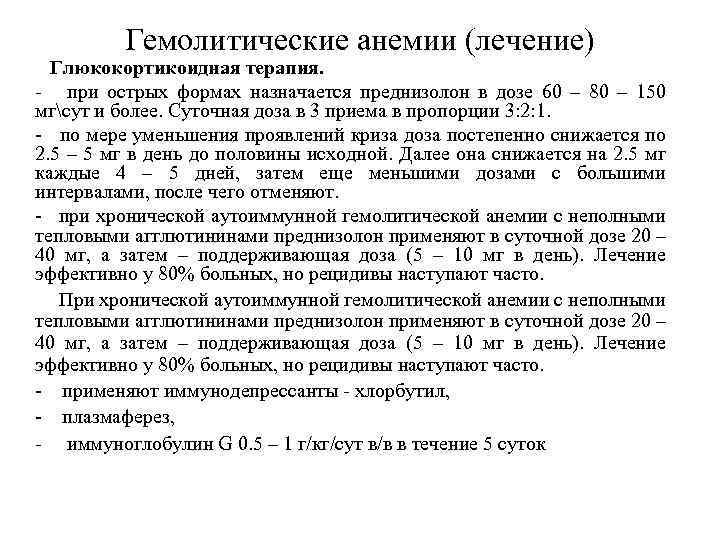

Гемолитические анемии (лечение) Глюкокортикоидная терапия. - при острых формах назначается преднизолон в дозе 60 – 80 – 150 мгсут и более. Суточная доза в 3 приема в пропорции 3: 2: 1. - по мере уменьшения проявлений криза доза постепенно снижается по 2. 5 – 5 мг в день до половины исходной. Далее она снижается на 2. 5 мг каждые 4 – 5 дней, затем еще меньшими дозами с большими интервалами, после чего отменяют. - при хронической аутоиммунной гемолитической анемии с неполными тепловыми агглютининами преднизолон применяют в суточной дозе 20 – 40 мг, а затем – поддерживающая доза (5 – 10 мг в день). Лечение эффективно у 80% больных, но рецидивы наступают часто. При хронической аутоиммунной гемолитической анемии с неполными тепловыми агглютининами преднизолон применяют в суточной дозе 20 – 40 мг, а затем – поддерживающая доза (5 – 10 мг в день). Лечение эффективно у 80% больных, но рецидивы наступают часто. - применяют иммунодепрессанты - хлорбутил, - плазмаферез, - иммуноглобулин G 0. 5 – 1 г/кг/сут в/в в течение 5 суток

Гемолитические анемии (лечение) Хирургическое лечение: - спленоэктомия применяется больным, вынужденным более 4 – 5 месяцев постоянно принимать преднизолон, имеющим частые рецидивы в течение года или перерывы в лечении преднизолоном не превышают 2 месяцев. спленэктомия дает положительный результат у 60% больных. - эмболизация сосудов селезенки, без операции выключает селезенку из общего кровотока. Цитостатическая терапия блокирует образование антител к эритроцитам, назначается при отсутствии эффекта от кортикостероидной терапии и спленоэктомии. Назначается азатиоприн (имуран) в суточной дозе 100 – 150 мг, циклофосфамид в дозе 400 мг в день, винкристин по 2 мг 1 раз в неделю, хлорбутин в суточной дозе 2. 5 – 5 мг. Лечение проводится до уменьшения гемолиза, чаще всего с преднизолоном, затем назначается поддерживающая доза (1/2 первоначальной). Курс лечения до 2 – 3 месяцев